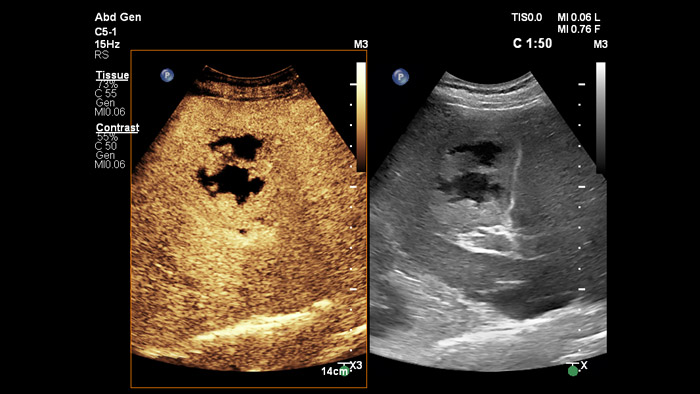

I mezzi di contrasto per l'ecografia possono trasformare il ruolo dell'ecografia, consentendo ai medici di studiare in tempo reale i margini di miglioramento delle lesioni epatiche. L'ecografia con mezzo di contrasto Philips è perfettamente integrata nel flusso di lavoro standard.